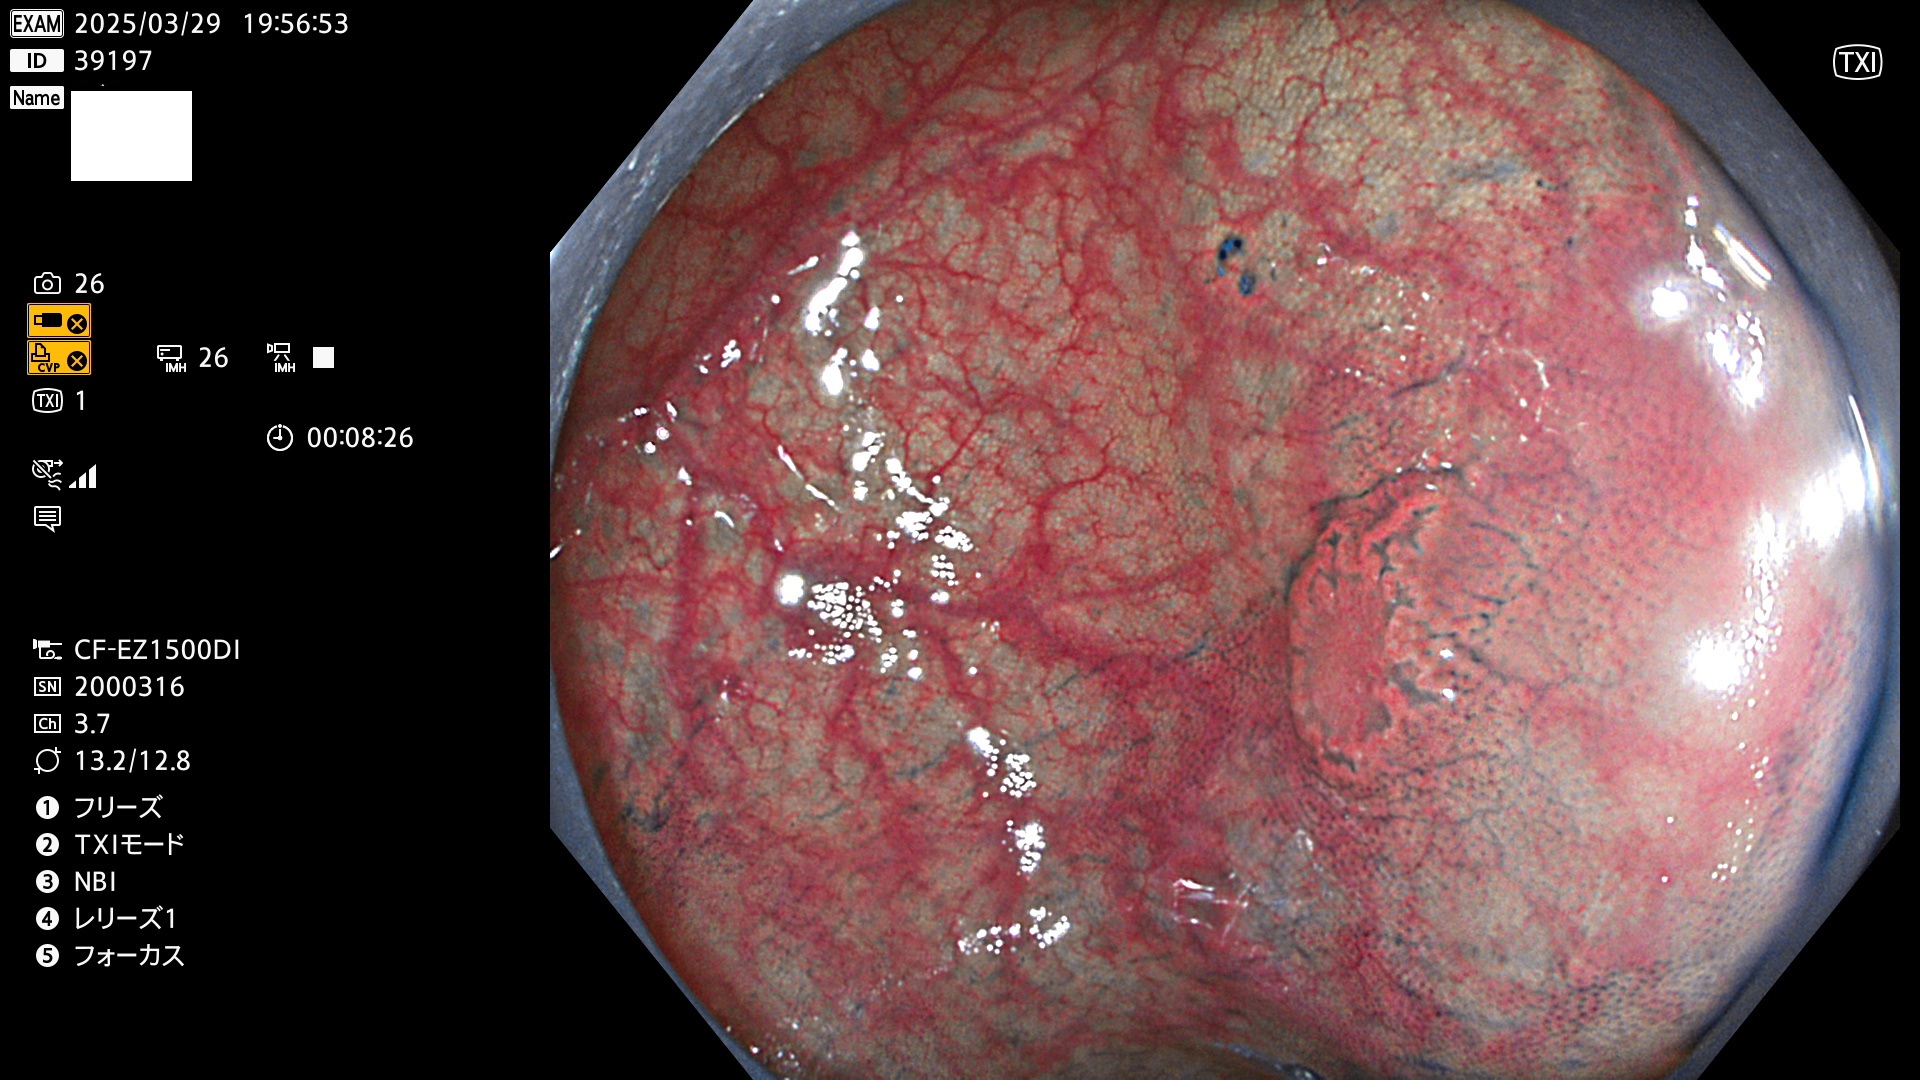

完全に平坦な物をUb、陥凹している物をUcと呼びます。Ubは認識が困難で、Ucはびらん(炎症)と紛らわしいために見落とされやすく、「内視鏡後・大腸癌」の原因になります。

抽出の対象期間 2025年3月27日〜3月30日の4日間(48件の検査)8個 (8/48=16%)